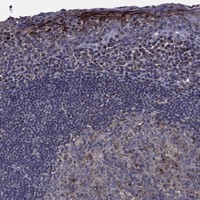

Immunohistochemical staining of human tonsil shows strong cytoplasmic positivity in subsets of germinal center, non-germinal center and squamous epithelial cells.